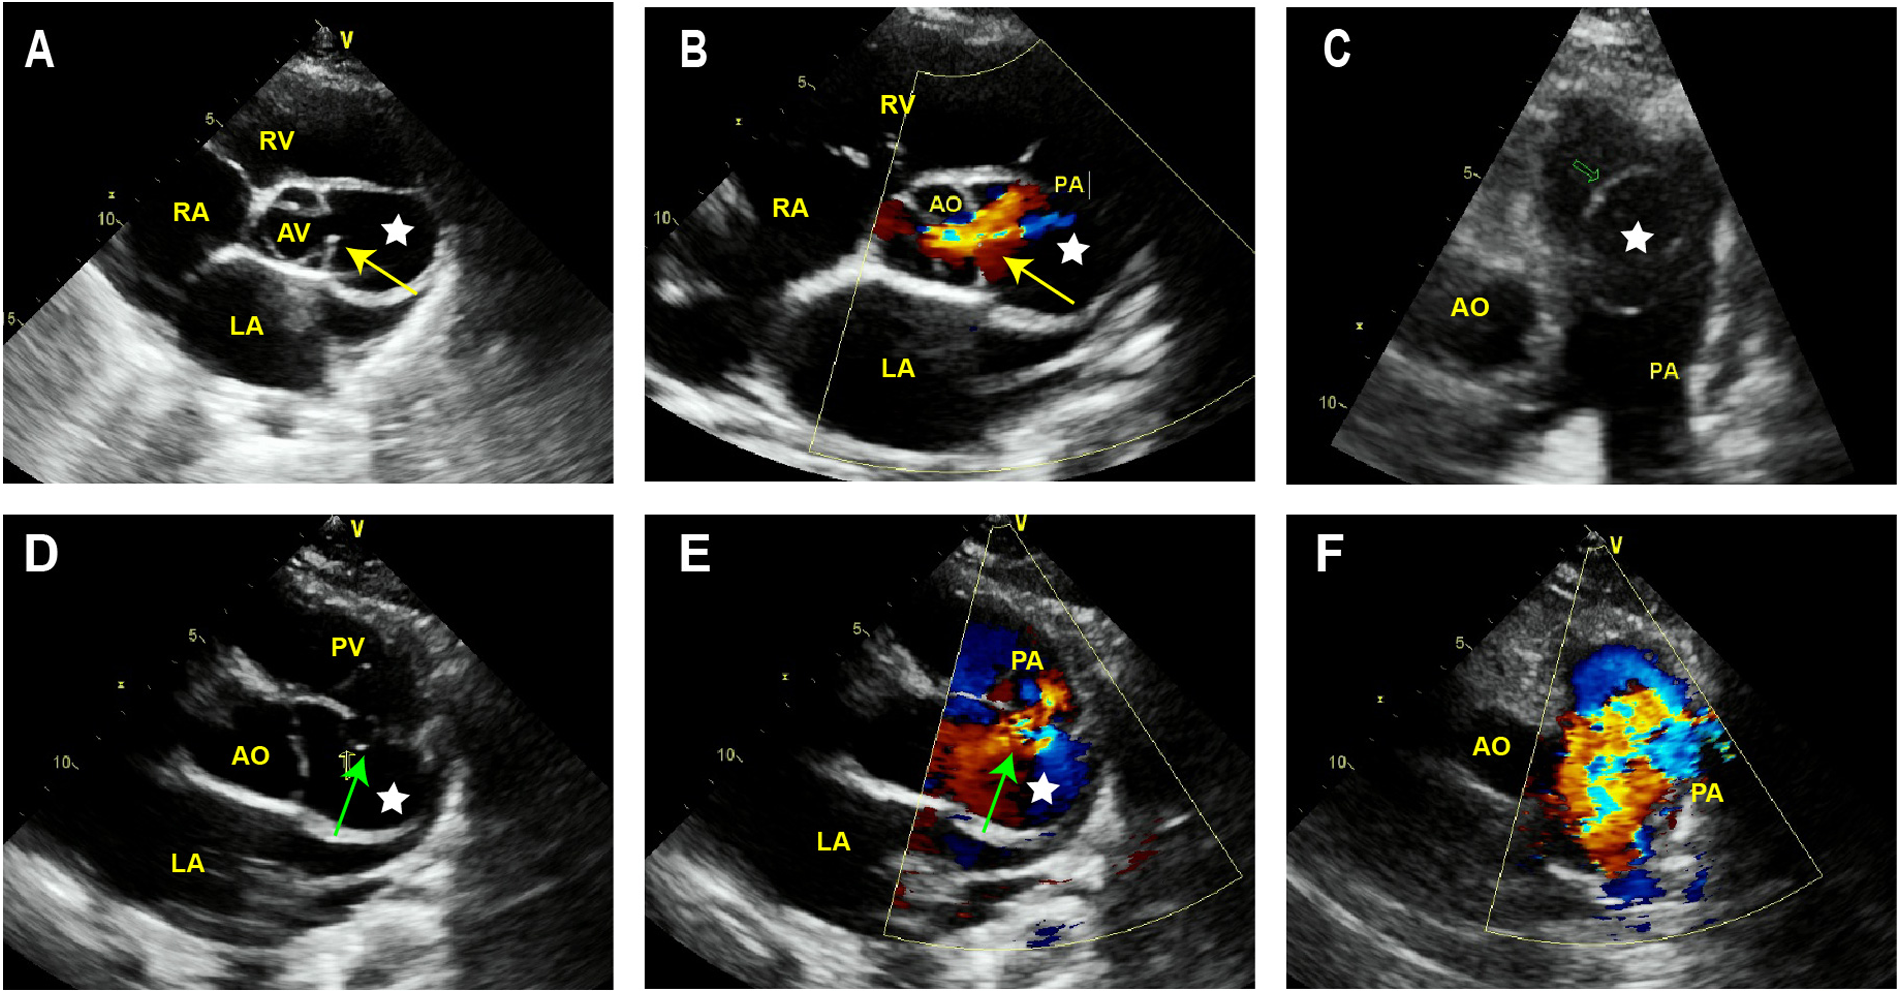

TTE revealed the presence of a left atrium and left ventricular enlargement, a left ventricular ejection fraction (LVEF) of 64%. We misdiagnosed the cystic structure communicating with the aorta through a channel with a width of approximately 7 mm on the side wall of the aortic valve ring (Figures 1A–C); and another communication port with a width of approximately 10 mm was also observed at the top of cystic structure, which connected to pulmonary artery (Figures 1D,E). The morphological changes of the cystic structure were not significant with respect to the contraction of the heart. Color Doppler imaging revealed that blood flowed through the communicating port into the capsule cavity during systole. Subsequently, the blood enters the pulmonary artery. Due to the presence of left to right shunting from the left ventricle to the pulmonary artery, the blood flow velocity in the pulmonary artery trunk increases rapidly, presenting a colorful mosaic-like blood flow signal (Figure 1F). CTA misdiagnosed as a SVA, approximately 4.1 × 3.2 cm in size, the width of the traffic area was approximately 8 mm (Figure 2). The main pulmonary artery was slightly widened, with a diameter of approximately 3.0 cm. Well visualization of the ascending aorta, descending aorta, left pulmonary artery, right pulmonary artery, brachiocephalic trunk, left common carotid artery, and proximal left subclavian artery, with smooth lumens and no stenosis or dilation. Digital subtraction angiography (DSA) revealed no significant stenosis or dilation in the right or left coronary arteries, and DSA suggested the presence of the diverticulum (Supplementary Figure S1). After completing relevant examinations after admission, including laboratory examination results exhibited elevated levels of some biomarkers like leukocyte (11.61 × 109/L; reference value 3.5∼9.5 × 109/L), C-reactive protein level (54.17 mg/L; reference value 0.068∼6.2 mg/L), hypersensitive troponin T (491 μg/L; reference value < 0.014 μg/L), N-terminal forebrain natriuretic peptide BNP (2,741 ng/L; reference value < 300 ng/L). Hepatitis B, hepatitis C, HIV antibodies and syphilis spirochete specific antibodies were negative and the patient's electrocardiogram results showed sinus rhythm. There were no obvious surgical contraindications, and she planed to undergo left ventricular diverticulectomy and pulmonary artery repair surgery. During surgery, a cystic diverticulum could be observed on the lateral wall of the left ventricular outflow tract (Figure 3A), extending toward the pericardial cavity and pulmonary artery. A communication port of approximately 8 mm (located below the aortic annulus) could be observed on the lateral wall of the left ventricular outflow tract and a rupture with a diameter of approximately 1 cm at the top of the capsule (Figure 3B; Supplementary Figure S2), communicating with the pulmonary artery. A continuous suturing technique using a 5-0 Prolene thread was employed to suture the communication port of the left ventricular outflow tract and the port of pulmonary artery rupture. Postoperative pathology revealed no epithelial lining in the capsule wall tissue. Myocardial cell atrophied and fibrosised, with some hyaline degeneration and local mucinous degeneration, consistent with changes in ventricular diverticulum (Figures 3C,D). After the surgery, the patient did not complain of any special discomfort. Her vital signs were stable, and her respiratory sounds were clear through auscultation in both lungs, without any dry or wet rales. There was no obvious murmur in the heart valves, and there was no swelling in the limbs. Postoperative echocardiography demonstrated that the left ventricle was still dilated, and the diverticulum collapsed without any residual shunts (Supplementary Figure S3).

Figure 1

Transthoracic echocardiography of LVD. (A) The short axis sections of the aorta depict a cystic structure (white star) between the aorta and pulmonary artery. (B) Color Doppler imaging reveals that in the systolic phase, blood exhibits a flow trajectory enters the capsule cavity via the established communication port. (C) The long axis section of the pulmonary artery demonstrates that the cystic structure protrudes into the pulmonary artery. (D,E) At the top of this cystic structure, a gap of approximately 10 mm width can be observed communicating with the lateral wall of the pulmonary artery. (F) Colorful embedded high-speed blood flow signals can be observed in the pulmonary artery. AV, aortic valve; AO, aorta; PA, pulmonary artery; PV, pulmonary valve; LV, left ventricle; LA, left atrium; RV, right ventricle; RA, right atrium.